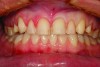

Fig 2. A preoperative retracted full-smile view. The restorations appear to be very “square” and “bulky.” The incisal embrasures are small, helping to make the teeth look uniform and square.

Figure 2

Preoperative Soft Tissue Correction

Figure 1 and Figure 2 show full-smile and intraoral full-arch views of the patient’s preoperative condition. The retracted full-smile image revealed disparate gingival heights over teeth Nos. 8 and 9. The proximal-facial line angles, particularly of the maxillary central incisors, were indistinct and rounded, contributing to a more “square” silhouette of the facial outline form. The maxillary anterior teeth appeared much larger in the cervico-incisal dimension with a dramatic decrease in height starting in the first premolar area (Figure 3). Esthetic harmony cannot always be achieved without addressing both hard and soft tissues and unfortunately, some clinicians “only see the white and not the pink.” The decreased height of the posterior teeth helped to contribute to the problem of the anterior teeth appearing too large. Prior to tooth preparation, a soft tissue correction was made with a diode laser (Picasso Diode Laser, AMD Lasers, amdlasers.com), which made the bulbous emergence profile of the existing veneer painfully evident. Because the patient had no second premolar due to extraction and orthodontics performed when the patient was younger, symmetry of the positions of the gingival margins was very important to the overall esthetics of the case. An imaginary line was drawn from the cervical height of contour of the maxillary cuspid to the gingival margin above the mesio-buccal root of the maxillary first molar. The gingival margin of the maxillary premolar needed to be on this line. If biologic width was violated, bony crown lengthening would be required (Figure 4). In this case, a closed-flap crown lengthening was performed with an ErCr: YSGG all-tissue laser (iLase® Plus, Biolase Technologies, biolase.com) to reestablish the proper 3-mm distance from the free gingival margin to the crest of bone. When healed, the new restoration would appear longer in the cervico-incisal dimension and gingival harmony would be achieved.